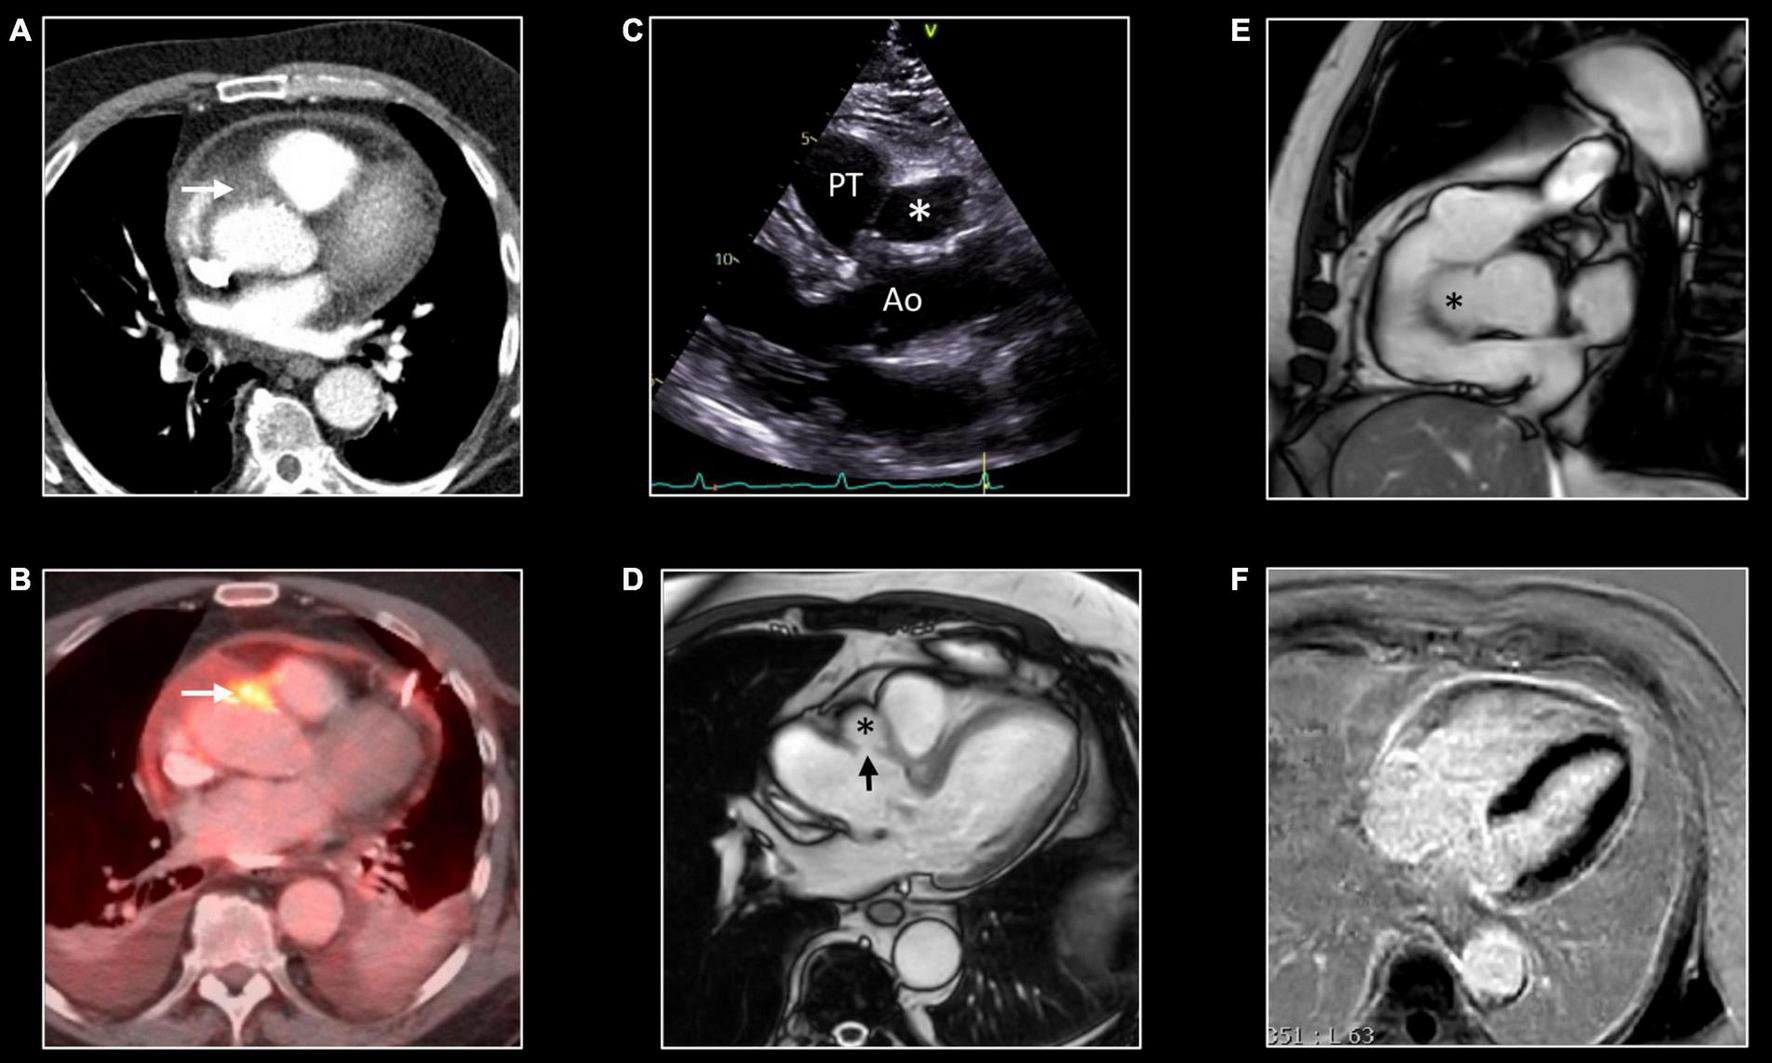

FIGURE 8

Cardiac sarcoidosis. Forty-three-year-old man known with systemic sarcoidosis admitted with recurrent ventricular tachycardia. Chest CT (A) shows enlarged mediastinal lymph nodes and perilymphatic micronodular pattern in left upper lobe (arrow), right middle and lower lobe. Fluoro-deoxy-gluclose (FDG) PET/CT shows multifocal FDG uptake in mediastinal and hilar lymph nodes (B), and strong multifocal uptake in the myocardium of left and right ventricle [arrows, (C,D)]. T2w-imaging shows myocardial edema, most pronounced in the apical half of a thickened ventricular septum [arrows, (E)] while LGE imaging shows multifocal, pronounced myocardial enhancement in left and right ventricle [arrows, (F)]. CMR and PET/CT findings are strongly suggestive of cardiac sarcoidosis with severe biventricular involvement. Cardiac biopsy showed granulomatous myocarditis. Because of the cardiac arrhythmias, the patient received an ICD implantation with several appropriate shocks. Unfortunately, the patient evolved toward biventricular heart failure for which he underwent a heart transplantation. Eight years later, the clinical history is uneventful.

FIGURE 10

False aneurysm of the thoracic aorta. Eighty-one-year-old man with MSSA sepsis and infectious pericarditis complicated by false aneurysm formation of the thoracic aorta. CT and PET/CT performed after pericardial drainage showed thickening of the pericardial layers with enhancement at chest CT (A) and FDG uptake at PET/CT. Note the presence of a focus of strong FDG uptake [arrow, (B)] with infiltration of the epicardial fat [arrow, (A)] at CT. These findings were interpreted as inflammation of one of the pericardial sinuses. However, follow-up transthoracic echocardiography, 3 months later, showed echo-lucent structure [*,(C)] between the aorta (Ao) and pulmonary trunk (PT). CMR shows the presence of a small pseudo-aneurysm [*,(D,E)] in communication with the thoracic aorta at the level of the sinotubular junction [arrow, (D)]. Note the residual enhancement of the pericardial layers at LGE imaging, (F) reflecting residual pericardial inflammation.